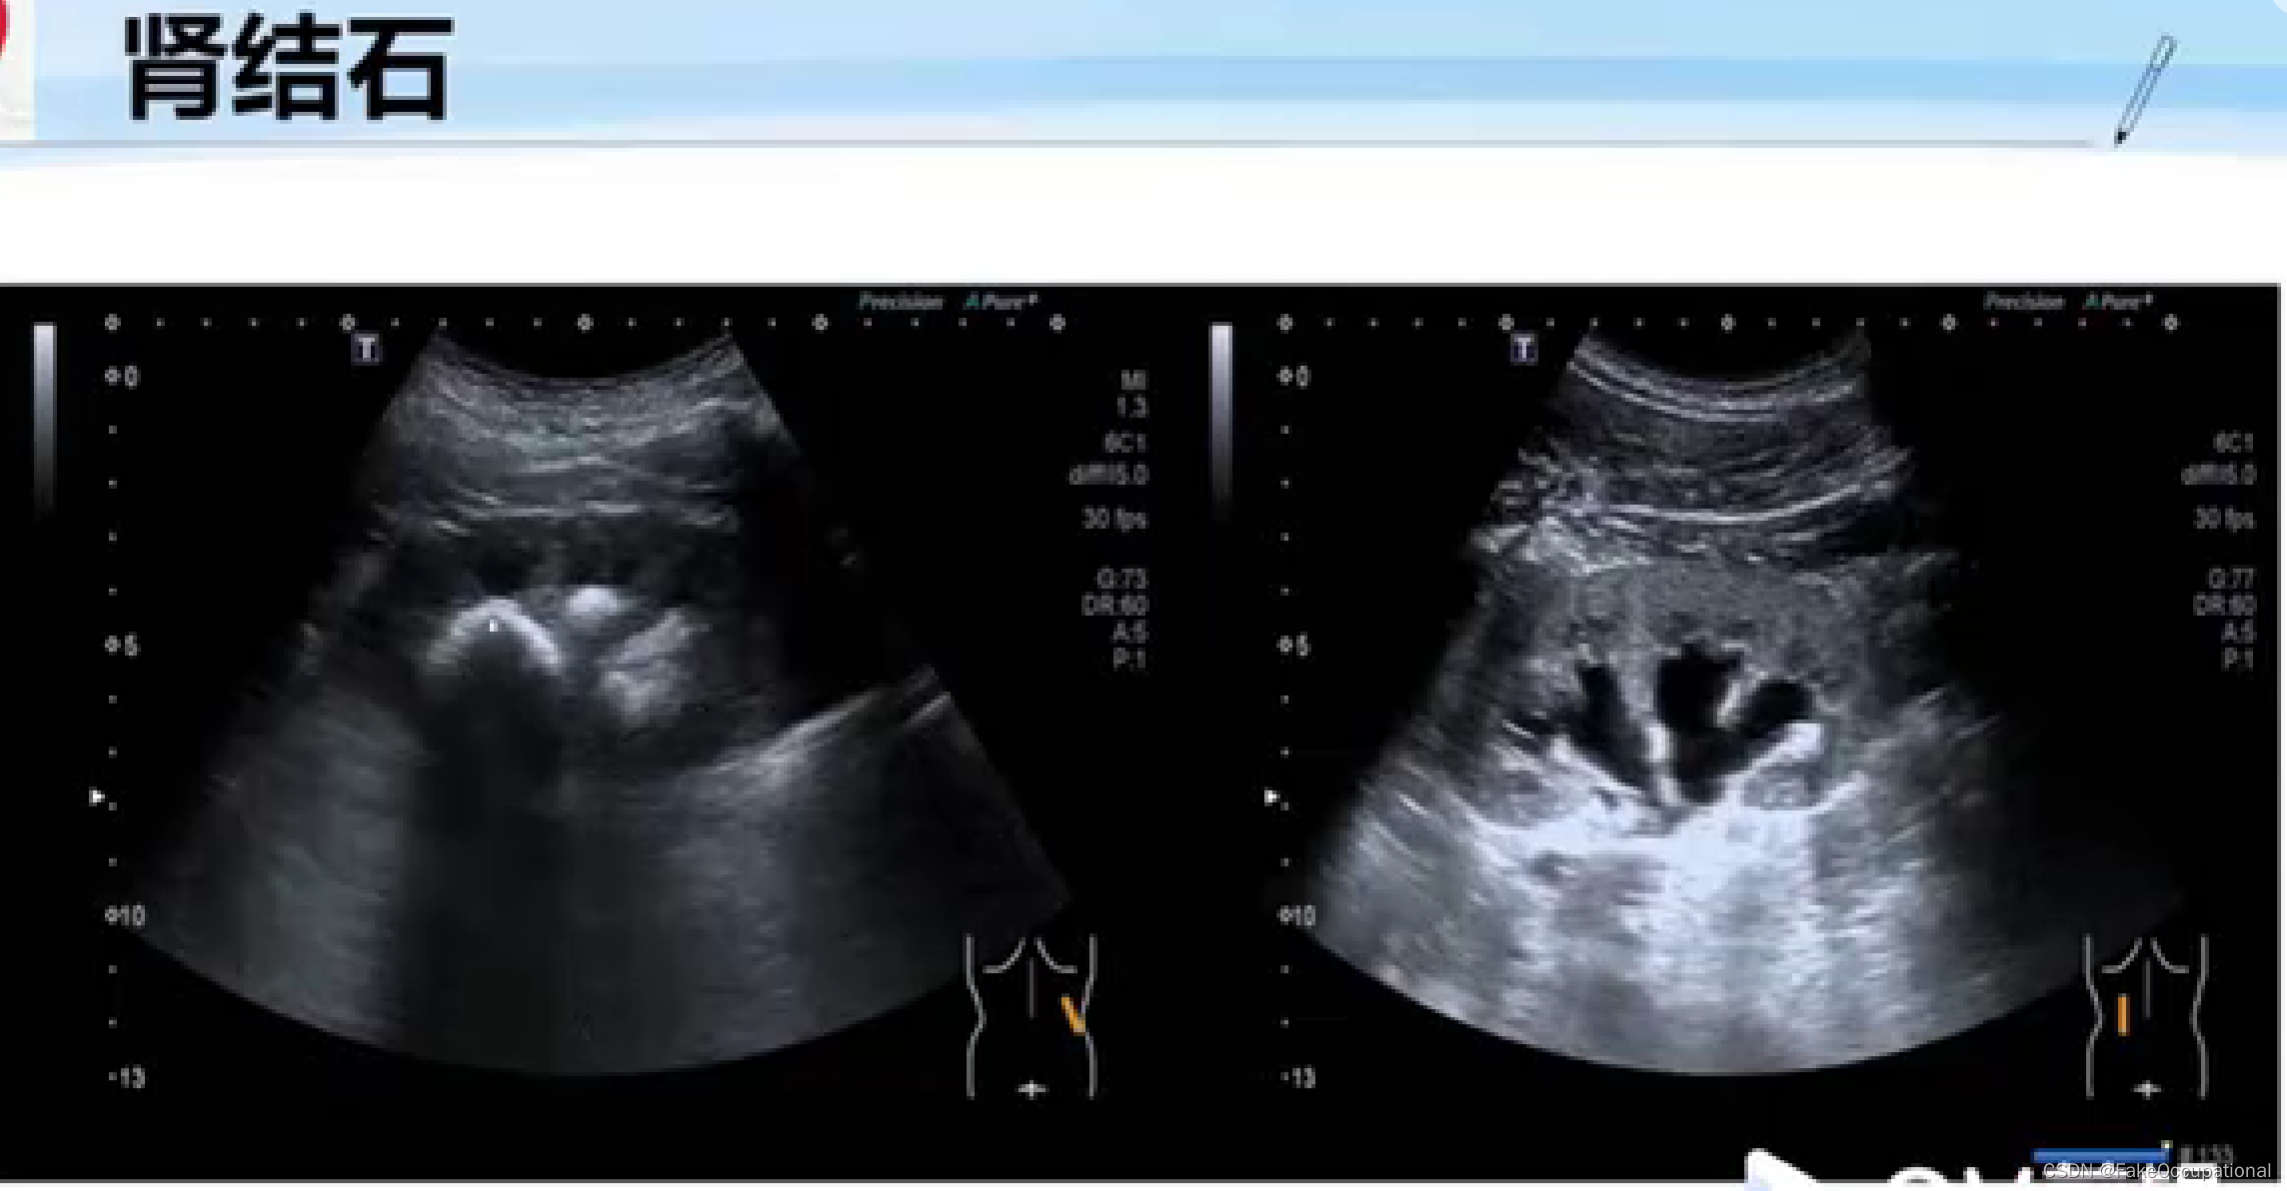

正常肾脏及肾血管超声表现

-

与正常肾脏造影相比,慢进快退

-

肾结核的超声显示的内部结构几乎完全消失

-

第三张图为CT结果